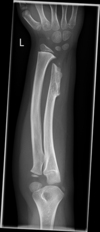

Madelung deformity. It comprises: (a) short distal radius, which shows a dorsal and ulnar curve;

(b) triangular shape of the distal radial epiphysis;

(c) premature fusion of the ulnar side of the distal

radial epiphysis;

(d) dorsal subluxation of the distal ulna;

(e) enlarged and distorted ulnar head; and

(f) wedging of the triangular-shaped carpus between the distal radius and ulna.

1. Isolated – bilateral > unilateral. Asymmetrical. Predominantly adolescent or young adult women.

2. Dyschondrosteosis (Leri–Weil disease) – bilateral with mesomelic limb shortening. AD. Predominantly men.

3. Diaphyseal aclasis.

4. Turner’s syndrome*.

5. Post-traumatic.

6. Postinfective.